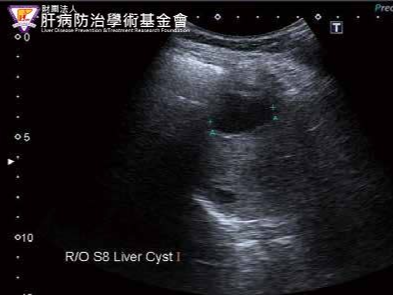

신장 및 요로계 질환

- 신장결석: 콩팥 내 결석 확인 가능

- 수신증: 요관 폐쇄 등으로 신장이 부어 있는 상태 확인

- 신장 종양, 낭종: 악성·양성 종양 여부 1차 판별